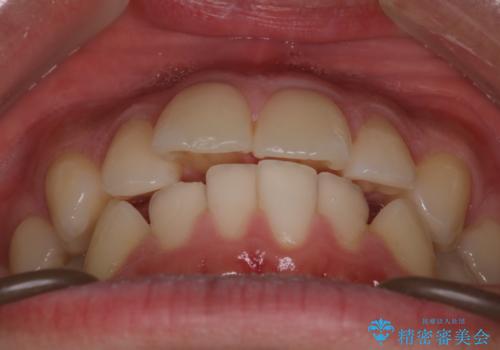

【インビザラインモニター】前歯が出ているのが気になる

- 上の前歯が出ているのが少し気になるとの事で来院されました。

インビザライン希望のため、IPR(歯と歯の間を削る処置)を行うことで、前歯の位置とがたつき整える治療計画を立てました。